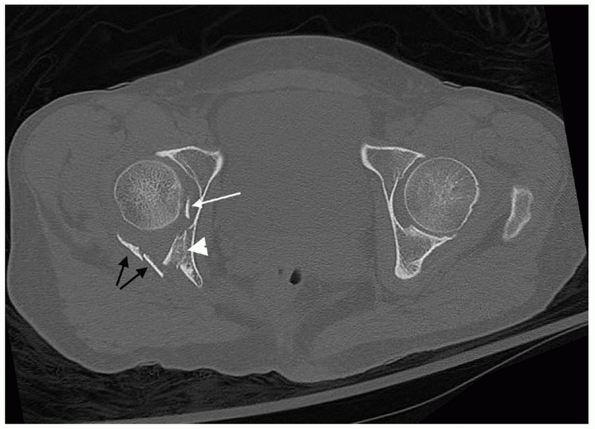

![]() |

FIGURE 45-12 Axial computed tomography section through the acetabulum. The right acetabular posterior wall is fractured (black arrows). There is an intra-articular loose body between the femoral head and acetabulum (white arrow). The asymmetry of the contour of the posterior wall from side to side is secondary to marginal impaction (white arrowhead),

which occurs when a segment of the articular surface and underlying cancellous bone adjacent to a major fracture line is impacted or depressed away from the normal contour of the joint. (Copyright Berton R. Moed, MD.) |